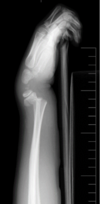

Cisto ósseo simples com fratura

Lesão litica unicameral.

Localização: úmero proximal e femur (< 20 anos) ou calcâneo, talus, ileo (> 20 anos).

Se fratura: Sinal do fragmento caído.